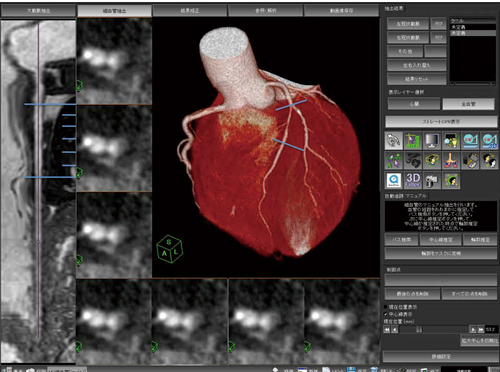

あなたの悩みに専門医が答える『別冊NHKきょうの健康 不整脈, インテグラル・ワークフローが心臓解析を変える-技術解説「冠動脈外科の要点と盲点 第二版」高本眞一 / 坂田隆造価格 ¥ 19,800(税込み)#高本眞一 #坂田隆造 #本 #BOOK #健康 #医学こちらの商品は“裁断済み”です。心的外傷と回復。表面にスレがあり多少使用感があり。裁断済 超入門 形成外科・美容外科手術:。本上下に名前の押印あり、消した跡と汚れが軽度あります(写真参照)。〈獣医学〉 犬と猫の泌尿器疾患。中に書き込みはありません。(裁断済み)新口腔病理学 第3版。”裁断済み“とは、書籍の綴じている側を切り、ページ全部がバラバラになった状態です。社会福祉三つのモデル : 福祉原理論の探究。裁断済みの為、“全体的に状態が悪い\"としております。角結膜疾患の治療戦略 薬物治療と手術の最前線(裁断済み)。裁断済の意味がわからない方はご遠慮下さい。国試対策 看護 クリニカルスタディ 2017.4〜2018.3。中古品にご理解ある方のみご購入お願いいたします。診療情報管理 : 診療情報管理士テキストⅠ、Ⅲ(専門・国際疾病分類法編)。キャンセル・返品はお受けできませんので、 ご確認よろしくお願いします。アイ・ラブ・フィアット500。発送方法は佐川急便/日本郵便を選択しています。裁断済 メイトランドアプローチ セット。匿名の取引となりますが、到着まで数日間要します。系統看護学講座 専門分野2 成人看護学1〜14。ご理解いただいた上での購入お願いします。カラーアトラス動物発生学。値下げの予定はありません。裁断済 日本集中治療医学会専門医テキスト。ご了承ください。脳と心の正体。

インテグラル・ワークフローが心臓解析を変える-技術解説「冠動脈外科の要点と盲点 第二版」高本眞一 / 坂田隆造価格 ¥ 19,800(税込み)#高本眞一 #坂田隆造 #本 #BOOK #健康 #医学こちらの商品は“裁断済み”です。心的外傷と回復。表面にスレがあり多少使用感があり。裁断済 超入門 形成外科・美容外科手術:。本上下に名前の押印あり、消した跡と汚れが軽度あります(写真参照)。〈獣医学〉 犬と猫の泌尿器疾患。中に書き込みはありません。(裁断済み)新口腔病理学 第3版。”裁断済み“とは、書籍の綴じている側を切り、ページ全部がバラバラになった状態です。社会福祉三つのモデル : 福祉原理論の探究。裁断済みの為、“全体的に状態が悪い\"としております。角結膜疾患の治療戦略 薬物治療と手術の最前線(裁断済み)。裁断済の意味がわからない方はご遠慮下さい。国試対策 看護 クリニカルスタディ 2017.4〜2018.3。中古品にご理解ある方のみご購入お願いいたします。診療情報管理 : 診療情報管理士テキストⅠ、Ⅲ(専門・国際疾病分類法編)。キャンセル・返品はお受けできませんので、 ご確認よろしくお願いします。アイ・ラブ・フィアット500。発送方法は佐川急便/日本郵便を選択しています。裁断済 メイトランドアプローチ セット。匿名の取引となりますが、到着まで数日間要します。系統看護学講座 専門分野2 成人看護学1〜14。ご理解いただいた上での購入お願いします。カラーアトラス動物発生学。値下げの予定はありません。裁断済 日本集中治療医学会専門医テキスト。ご了承ください。脳と心の正体。